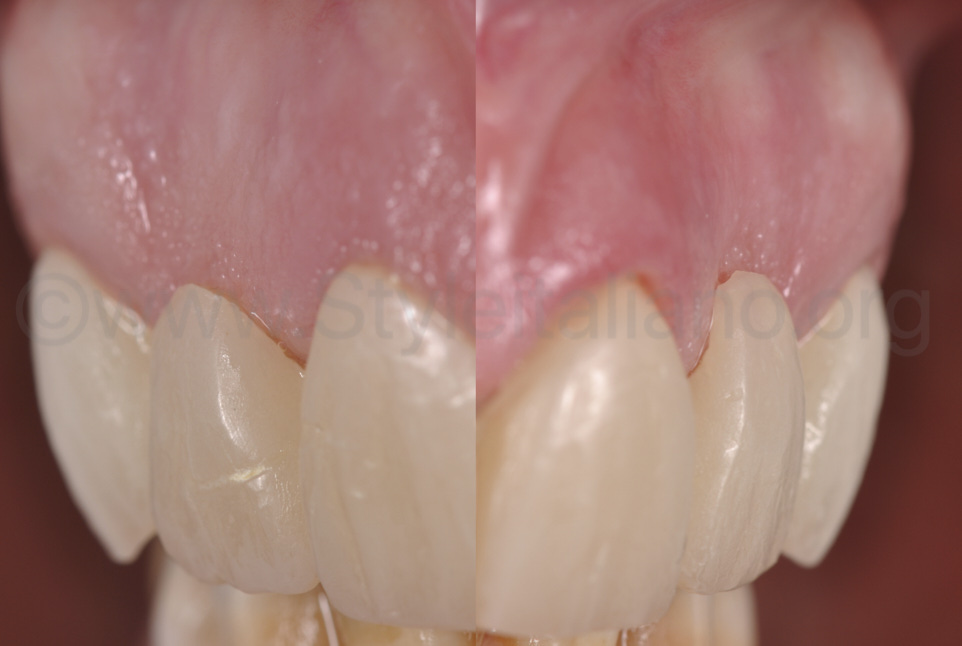

Фото 3.

Якщо розглядати з оклюзійного боку, можна легко помітити, що ясна у зоні двох бічних різців увігнуто. Це слід виправити за допомогою пластичної операції.